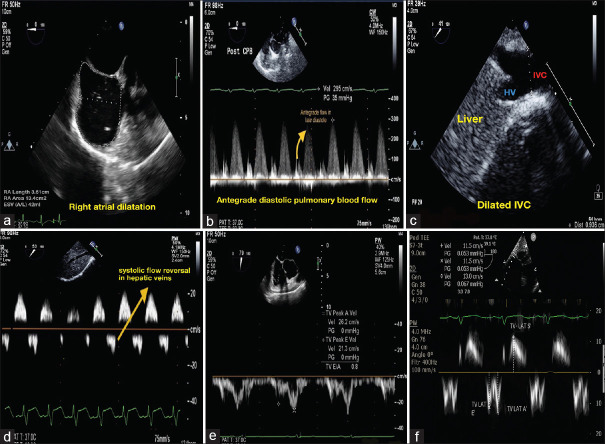

Methods: This prospective, observational study was done at a tertiary care hospital involving 40 pediatric TOF patients aged less than 2 years who underwent complete intracardiac repair with cardiopulmonary bypass (CPB). Echocardiographic observations were made using a pediatric transesophageal echocardiography probe after surgical repair in the post-CPB period. The ASE-described parameters (late diastolic forward flow in the main pulmonary artery, right atrial dilatation, inferior vena cava dilatation, and hepatic venous flow reversal) were acquired to diagnose the RVDD. The tricuspid Doppler parameters (E/A and E/E') were measured, and its predictive ability to diagnose RVDD was analyzed and compared with the ASE criteria.

Results: Based on the ASE criteria, 13 patients (32.5%) were diagnosed to have RVDD. We found that an E/E' ratio of ≥ 6.26 and an E/A ratio of >1.34 can be taken as the cutoff for diagnosing the RVDD. Based on the tricuspid Doppler parameters (E/A > 1.34 and E/E' >6.26), 17 patients (42.5%) were diagnosed to have RVDD, which was comparable to that of the diagnosis by ASE criteria (P > 0.05).